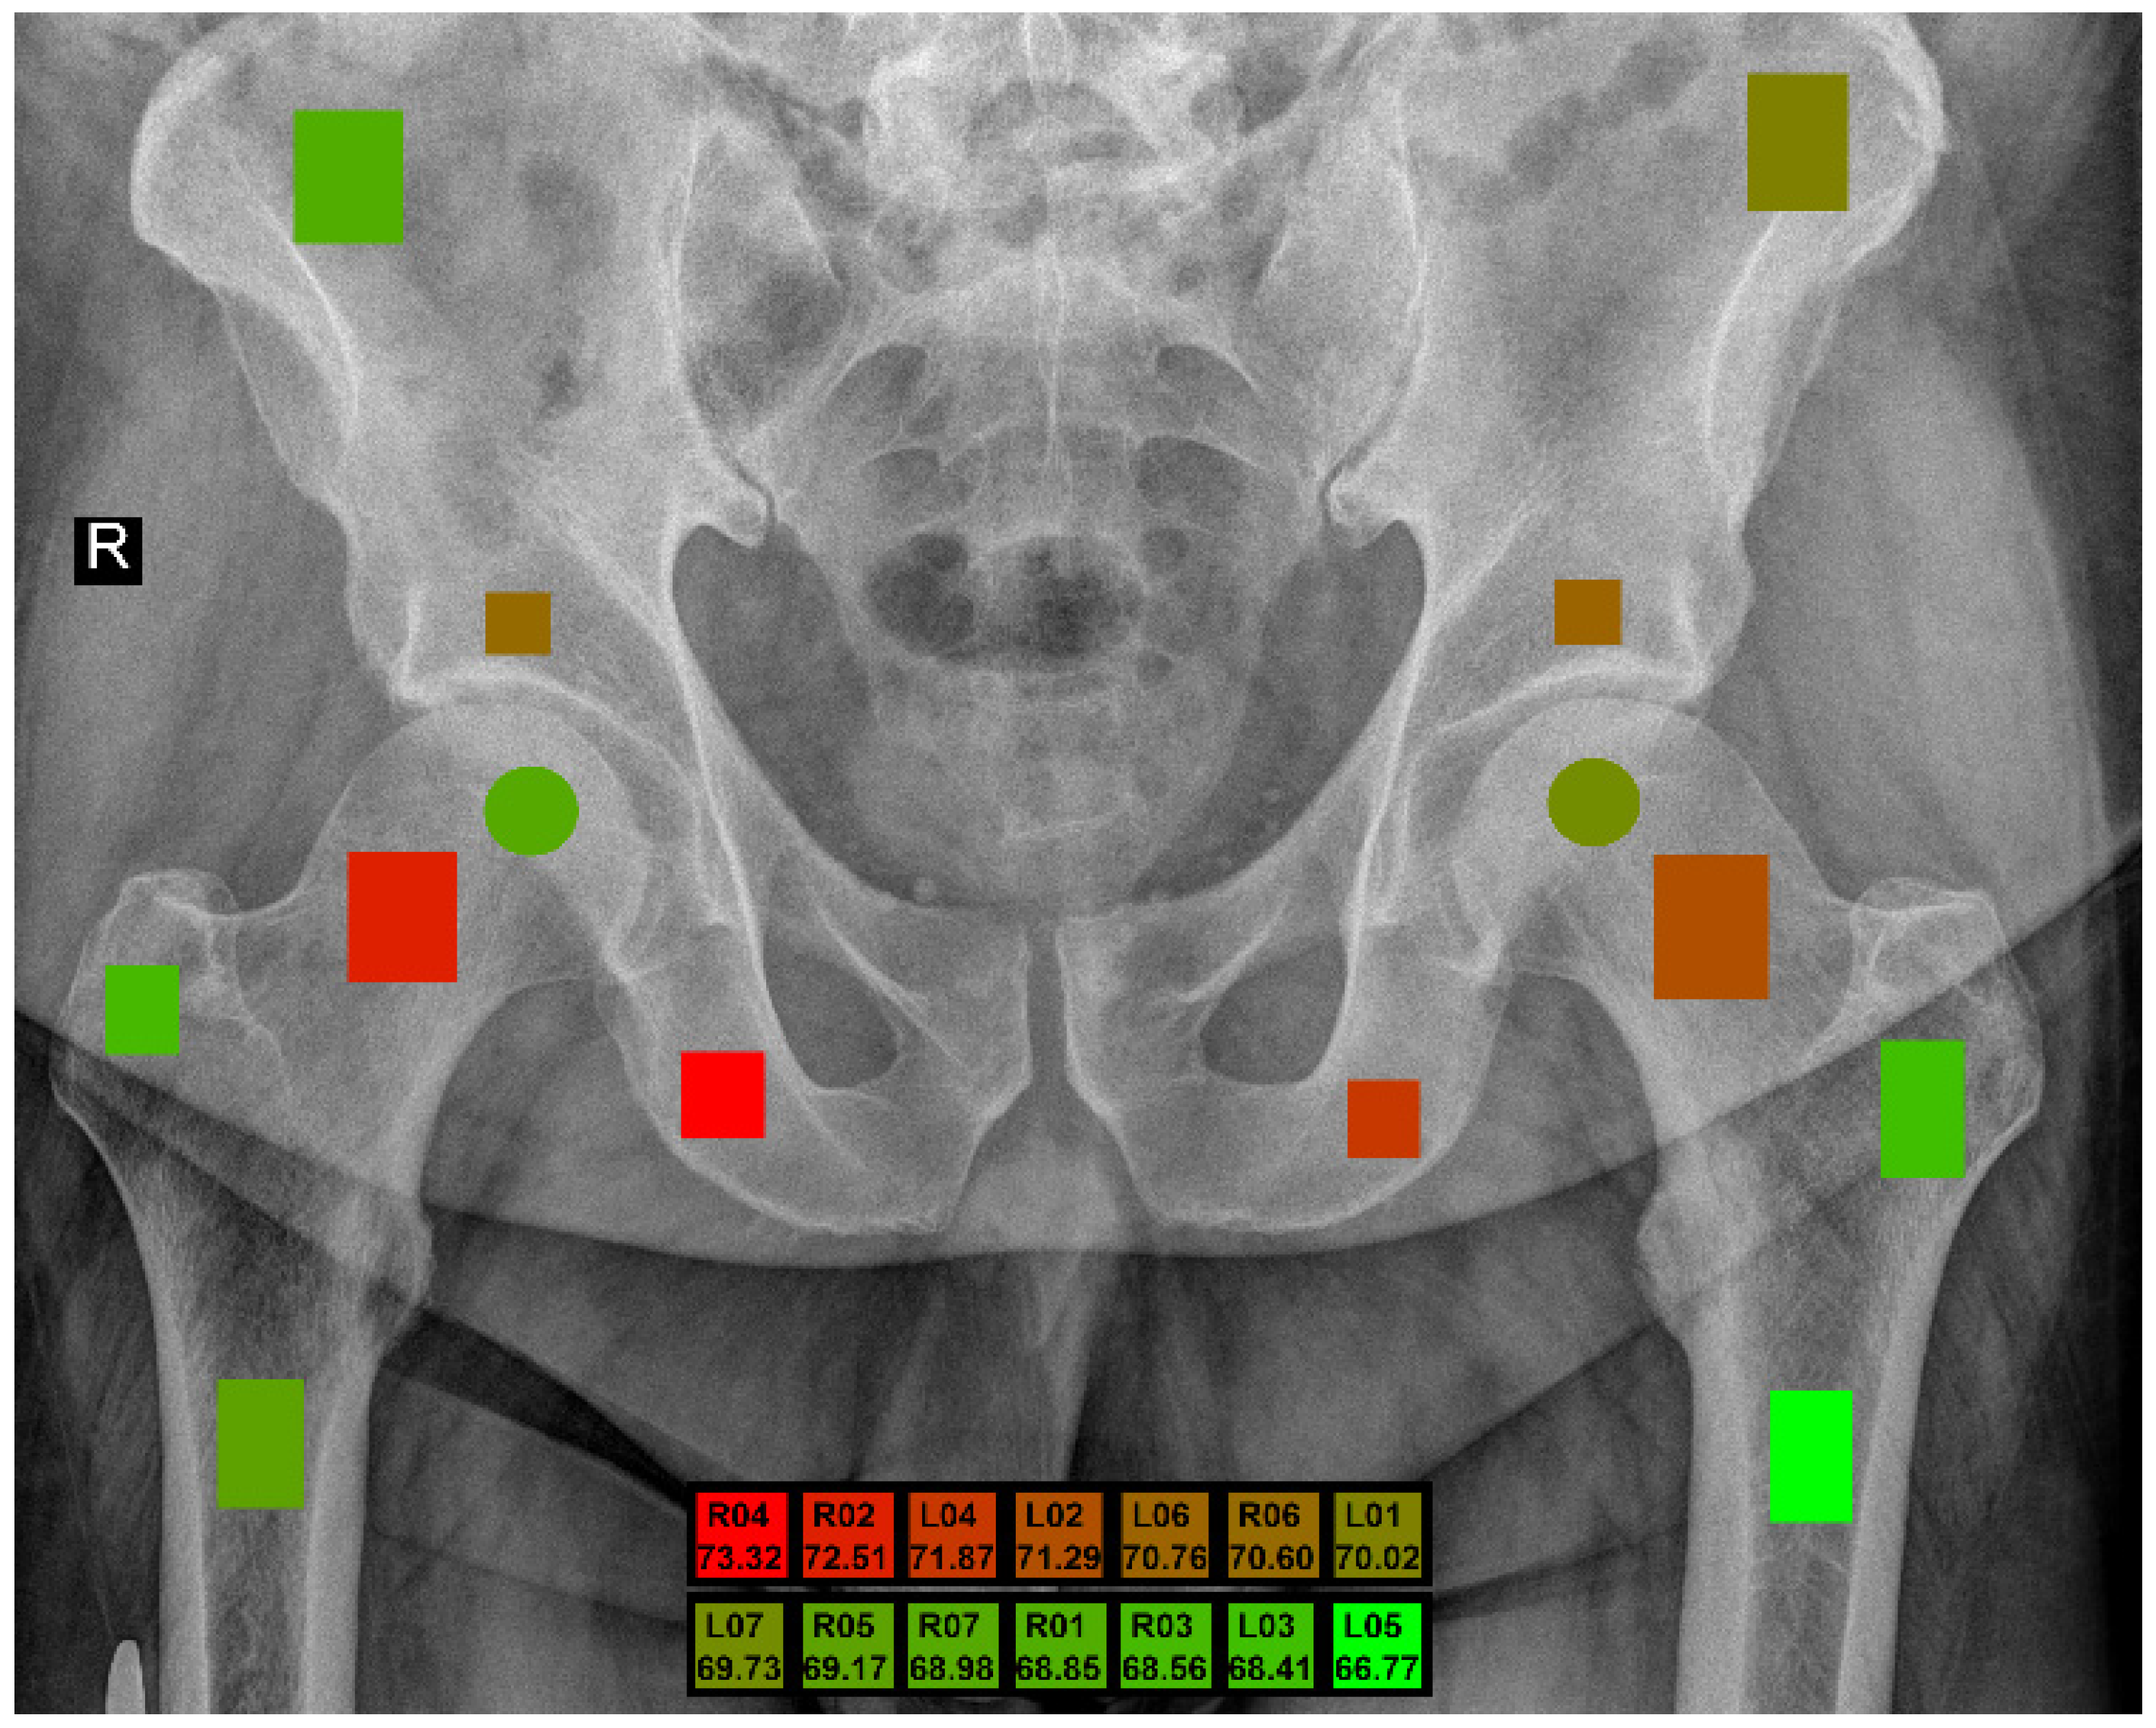

| ROI Left | ROI Right | Anatomical Structure |

|---|---|---|

| L01 | R01 | Wing of ilium |

| L02 | R02 | Neck of femur |

| L03 | R03 | Greater trochanter |

| L04 | R04 | Ischium |

| L05 | R05 | Shaft of femur |

| L06 | R06 | Hip bone above the acetabulum |

| L07 | R07 | Femur head (center) |

| ROI | 5 Bit | 6 Bit | 7 Bit | 8 Bit | Max | Avg |

|---|---|---|---|---|---|---|

| L01 | 66.23 | 68.86 | 69.19 | 70.02 | 70.02 | 68.58 |

| L02 | 71.29 | 70.46 | 70.03 | 70.26 | 71.29 | 70.51 |

| L03 | 68.10 | 68.41 | 67.41 | 68.01 | 68.41 | 67.98 |

| L04 | 71.87 | 71.46 | 71.21 | 71.37 | 71.87 | 71.48 |

| L05 | 64.99 | 66.77 | 63.63 | 63.63 | 66.77 | 64.76 |

| L06 | 70.76 | 68.31 | 68.72 | 69.11 | 70.76 | 69.23 |

| L07 | 69.65 | 69.59 | 69.73 | 69.16 | 69.73 | 69.53 |

| R01 | 67.04 | 68.85 | 67.34 | 66.81 | 68.85 | 67.51 |

| R02 | 71.78 | 71.59 | 72.51 | 71.30 | 72.51 | 71.80 |

| R03 | 68.56 | 66.46 | 67.47 | 68.38 | 68.56 | 67.72 |

| R04 | 73.32 | 70.48 | 72.64 | 71.30 | 73.32 | 71.94 |

| R05 | 69.17 | 67.42 | 67.57 | 68.98 | 69.17 | 68.29 |

| R06 | 67.92 | 68.78 | 70.60 | 69.11 | 70.60 | 69.10 |

| R07 | 66.70 | 67.40 | 68.98 | 67.27 | 68.98 | 67.59 |